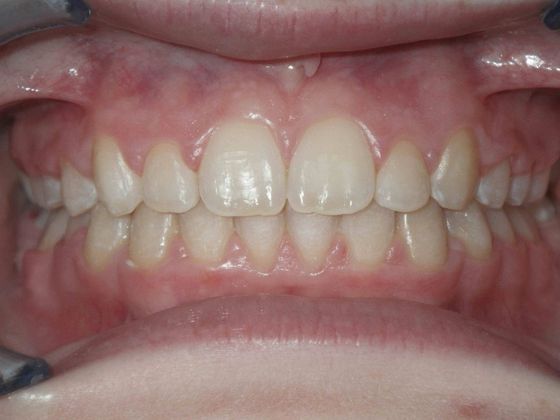

Orthodontics: Case 2

Patient is 9 years old and presents with 100% overbite and blocked out upper and lower lateral incisors. Both upper central incisors are palatally inclined causing a lack of space available for most anterior teeth. Advised her parents that she needs Phase I Interceptive Orthodontic treatment to provide room for all upper and lower front teeth. Phase I treatment was begun and finished, then began Phase II treatment shortly thereafter to finalize case. Removable retainer were fabricated for retention.